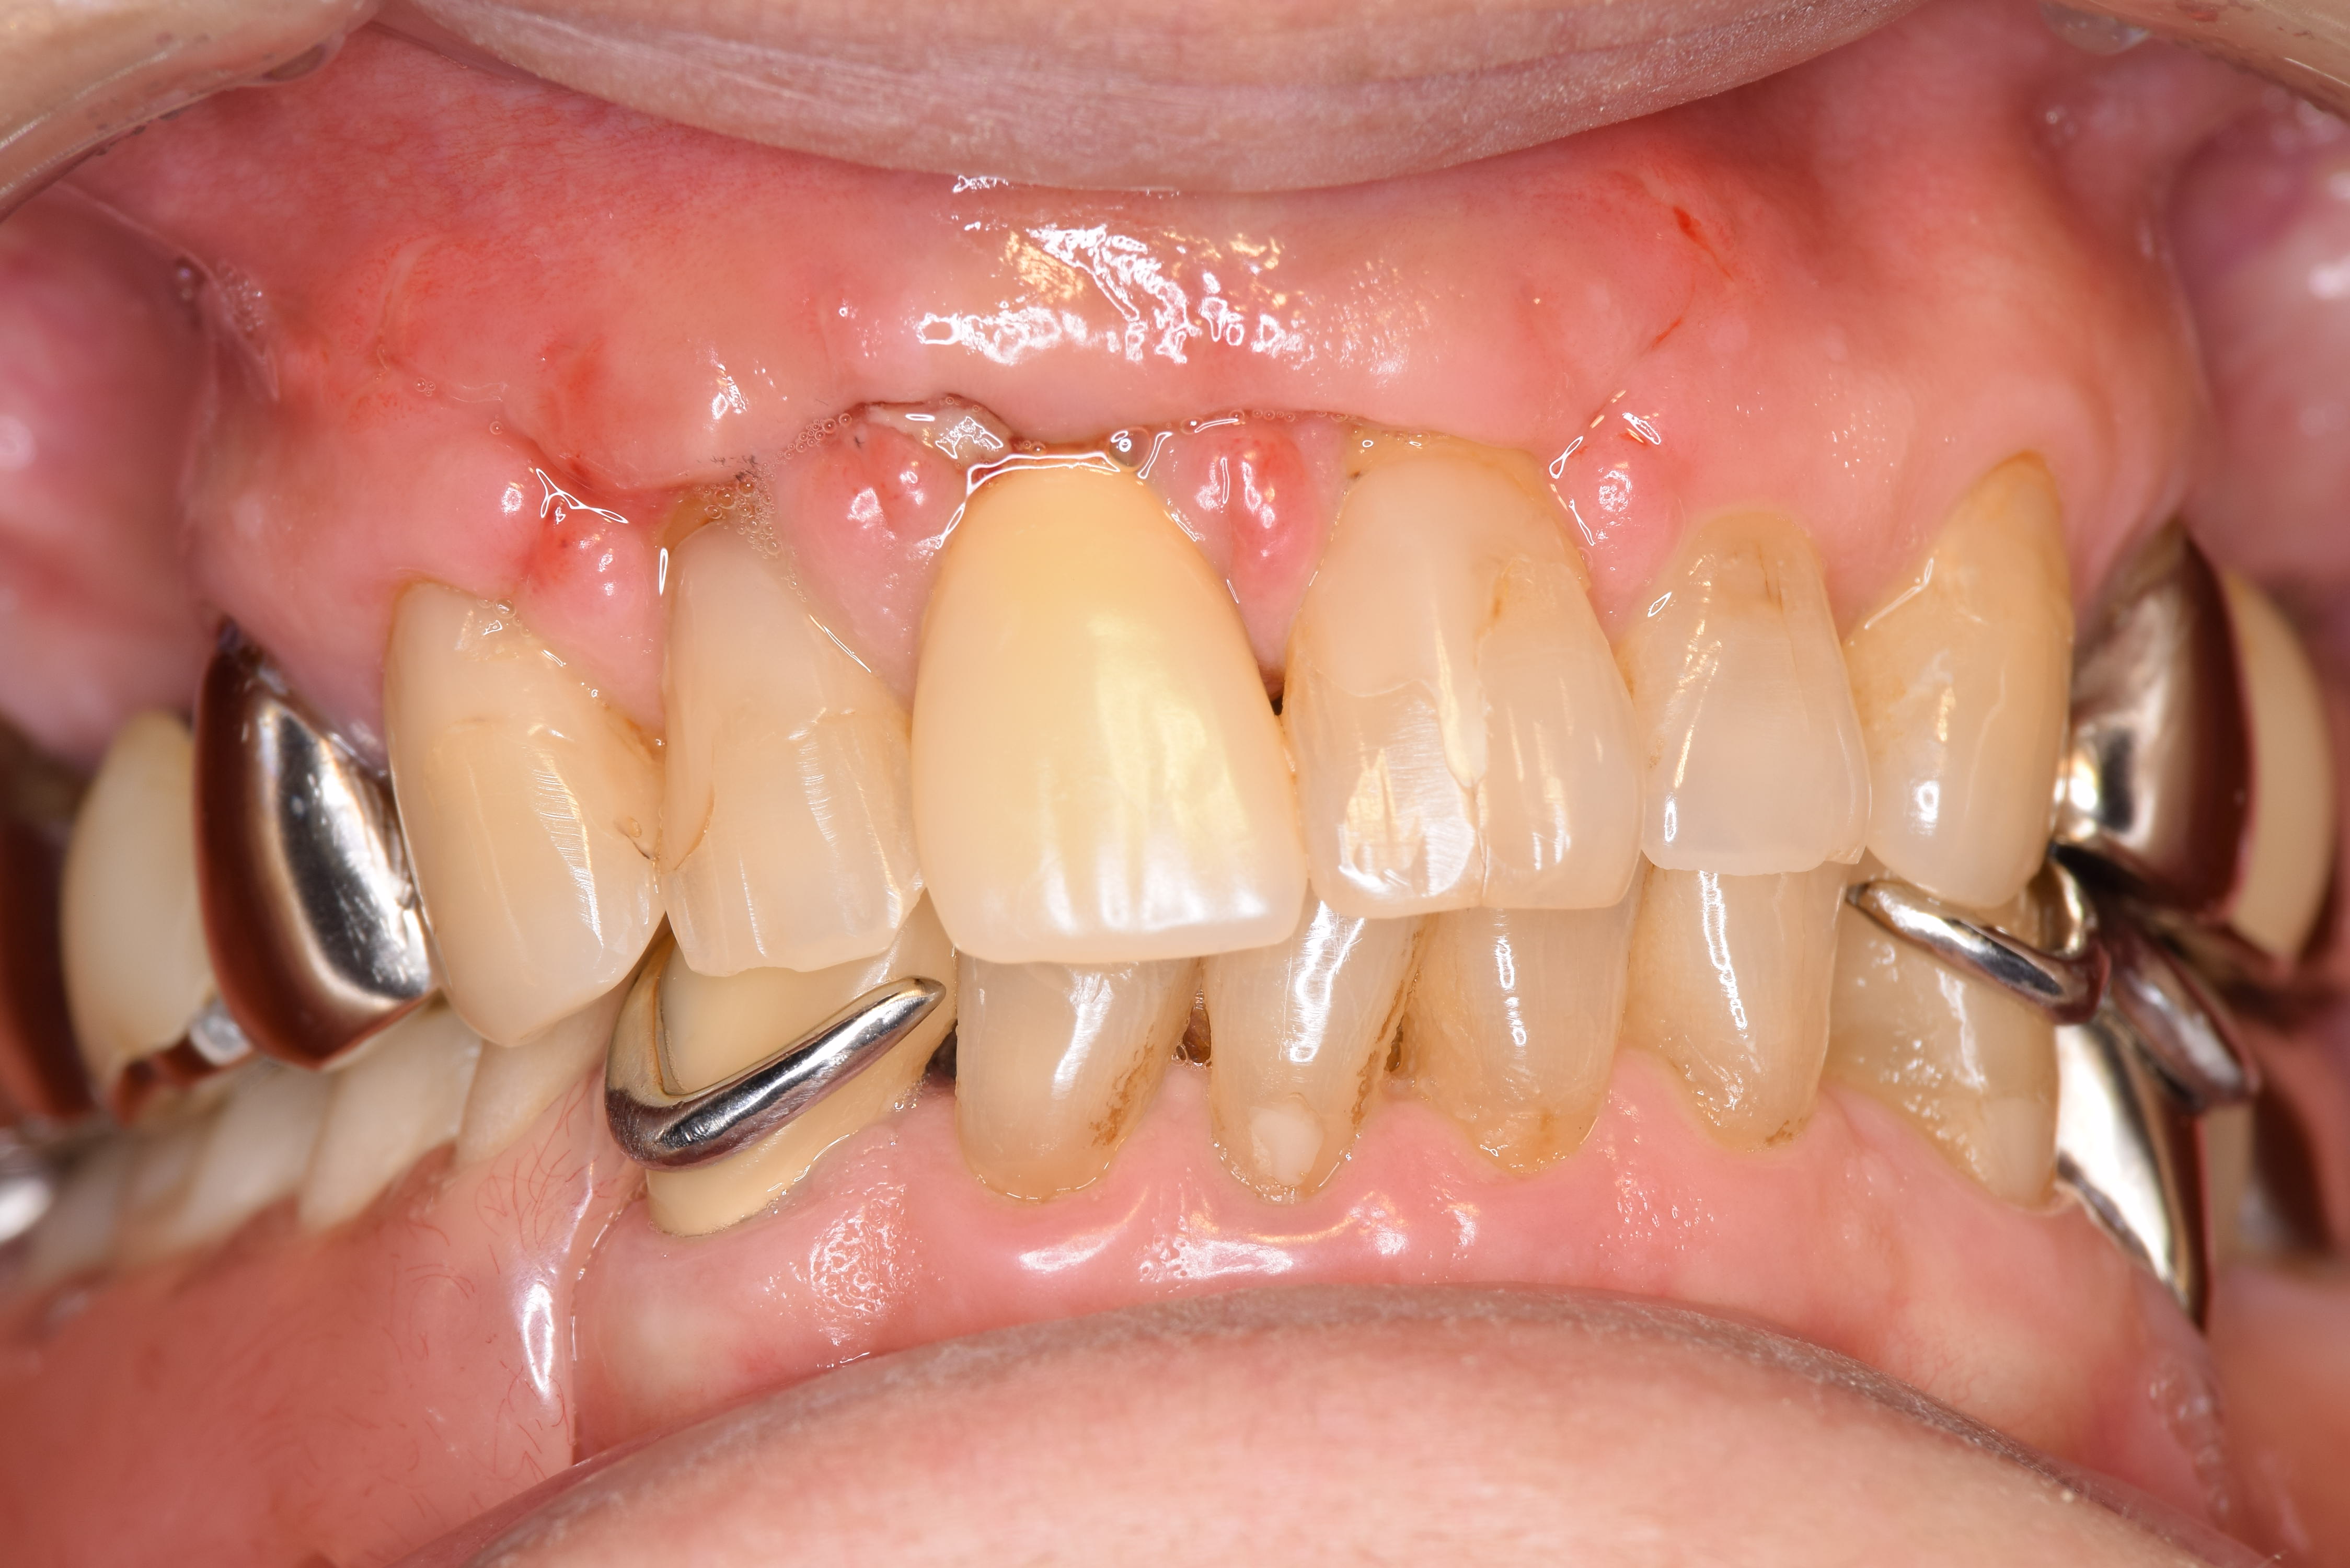

右上1番の根の先の部分に腫れと瘻孔(膿の出る穴)があります。